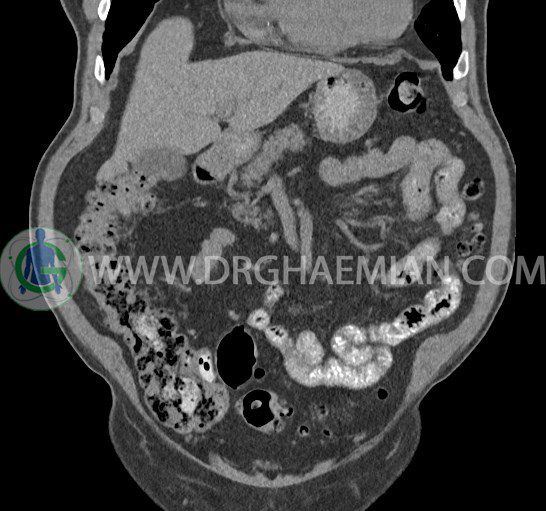

سی تی اسکن لگن یکی از روش های تصویربرداری با سی تی اسکن است. این روش با استفاده از تشعشعات تصاویر عرضی از ناحیه شکمی ایجاد میکند. در این کیس ديورتيكولوزيس، کیست های کورتیکال در هر دو کلیه، لنفادنوپاتی، کلسیفیکاسیون دیواره آئورت و شریان ایلیاک، تغییرات DJD ناحیه توراکولومبار و پروستات بزرگتر از عادی دیده می شود.

در سي تي اسکن اسپيرال شکم و لگن با و بدون کنتراست خوراکی و وريدی (مولتي ديدکتور 16 با مقاطع ظريف و بازسازي هاي ساژيتال و کرونال):

– کيست هاي کورتيکال ساده به قطر 5 mm تا 50 mm در کليه راست و به قطر 5mm تا 55 mm در کليه چپ

– توده ايزودنس به ابعاد mm 17 x 28 در پره ائورت مجاور قسمت تحتاني D3 دئودنوم مطرح کننده لنفادنوپاتي و با احتمال کمتر آنوريسم ترومبوزه (نيازمند مطابقت سونولوژيک)

– کلسيفيکاسيون ديواره آئورت و شريان ها ايلياک همراه با نشانه هاي ترومبوز مورال در بيفورکاسيون ائورت با امتداد به پروگزيمال هاي شريان هاي ايلياک

– ديورتيكولوزيس در کولون نزولي وسيگموئيد

لنفادنوپاتي به ابعاد mm 22 x 25 مجاور شريان ايلياک خارجي چپ و به ابعاد mm 17 x 28 مجاور شريان ايلياک خارجي راست

– تغييرات DJD در ناحيه توراکولومبار و

– پروستات به ابعاد mm 45 x 54، بزرگ تر از نرمال

مشهود است.